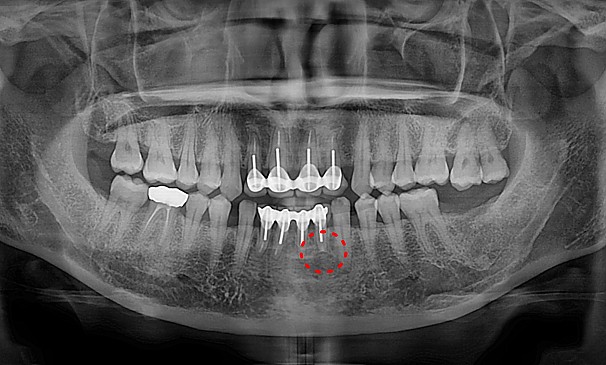

병든 뿌리 절제술

배OO님 전후사진 | 치료 기간 : 1주

치료 전

치료 후